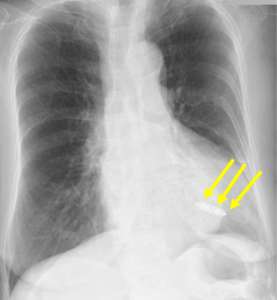

では、もう一つ。下のレントゲンもペースメーカが入っている患者さんのものですが、ペースメーカがどこにあるか分かるでしょうか?

答えは矢印のところです。

これがリードレスペースメーカですが、ペースメーカが植え込まれている情報が無かったり、撮影条件によっては、編集長も見落としそうになることもあります。従来のものと比べた写真が下のものです。

このリードレスペースメーカは、登場した当初はVVIのみでしたので、徐脈性心房細動や高齢者に用いられることが多かったのですが、現在はVDDのものやスクリューで固定するタイプのものが登場して、以前とは適応も変わってきています。あなたもどこかで目にすることがあると思いますので、今回は基本的なところを紹介します。